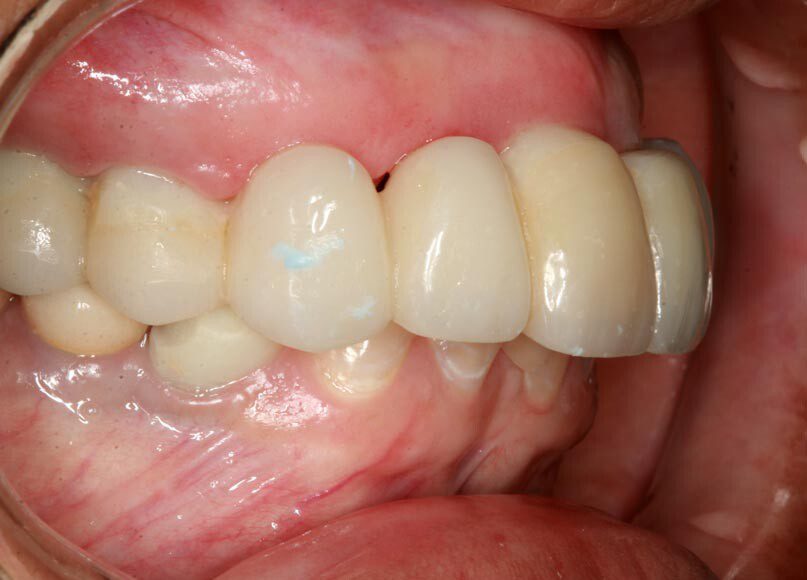

Smile GalleryImplant RestorationsFull Mouth Implant Restoration Full arch zirconia implant bridge (full smile) 1 of 37 Pre-op full smile Pre-op lips retracted Pre-op panoramic x-ray Extraction of strategic teeth Placement of implants Extraction of some remaining teeth after verification of adequate implant stability Occlusal view Post-op panoramic x-ray Immediately fabricated provisional restoration (tissue side view) Immediately fabricated provisional restoration (occlusal side view) Immediate provisional delivered on day of surgery Immediate provisional 2 weeks later Scalloped tissue developed from the provisional at 2 weeks Jig used for making a master impression Provisional in place (full smile) Provisional in place (lips retracted) Provisional in place (right side) Provisional in place (left side) Wax try-in (full smile) Wax try-in (right side full smile) Wax try-in (left side full smile) Wax try-in (full face, lips together) Wax try-in (full smile) Wax try-in (right side) Wax try-in (left side) Wax try-in (lips retracted) Full arch zirconia implant bridge on master cast (frontal view) Full arch zirconia implant bridge on master cast (occlusal view) Implant positions and soft tissue representation on master cast (occlusal view) Soft tissue representation on master cast (frontal view) Full arch zirconia implant bridge (tissue side view) Soft tissues on day of delivery (occlusal view) Soft tissues on day of delivery (frontal view) Full arch zirconia implant bridge delivered (lips retracted) Full arch zirconia implant bridge (lips retracted, close up) Post treatment panoramic x-ray Full arch zirconia implant bridge (full smile)